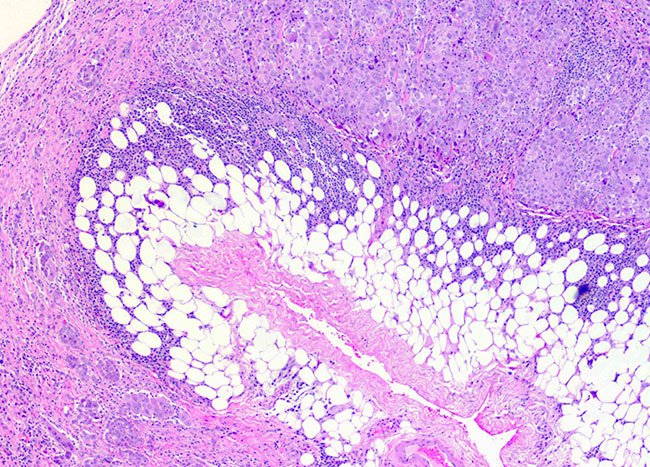

- Next, a pathologist examines the physical characteristics of the cells under a microscope as well as how the cells are ordered.

- This allows the growth to be identified as mesothelial or lung cancer cells.

- The biopsy can also identify if the cells are epithelial or sarcomatoid. If epithelial cells are found, the pathologist will then determine which subtype they are.

All types of mesothelioma are difficult to diagnose. The work of the pathologist is essential to identifying cell types. This part of the diagnosis helps doctors determine the best course of treatment. If you’re not comfortable with a diagnosis, seek a second opinion.